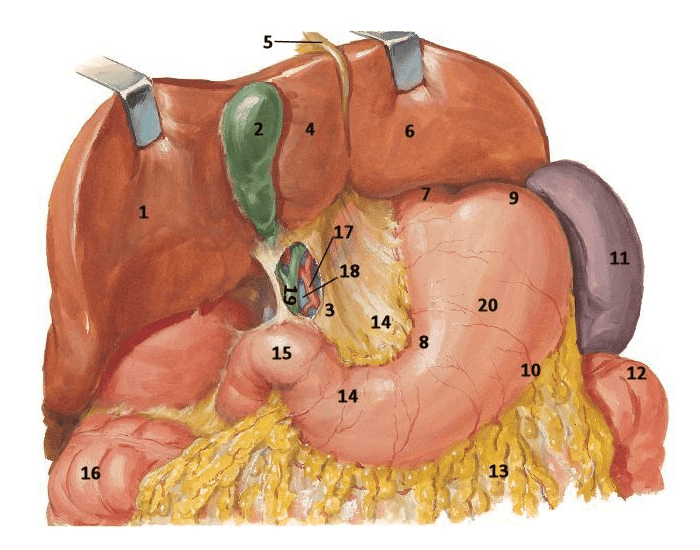

Раздел: Фотопанорама